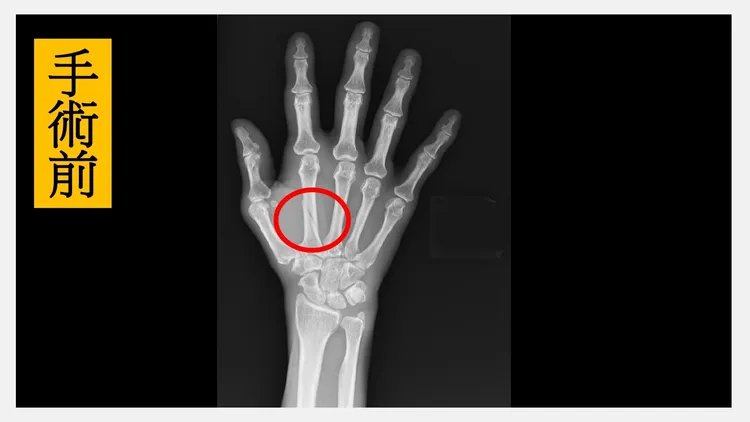

手術前X光片發現,病患的右手第二掌骨粉碎性骨折合併錯位(紅圈處)。院方提供